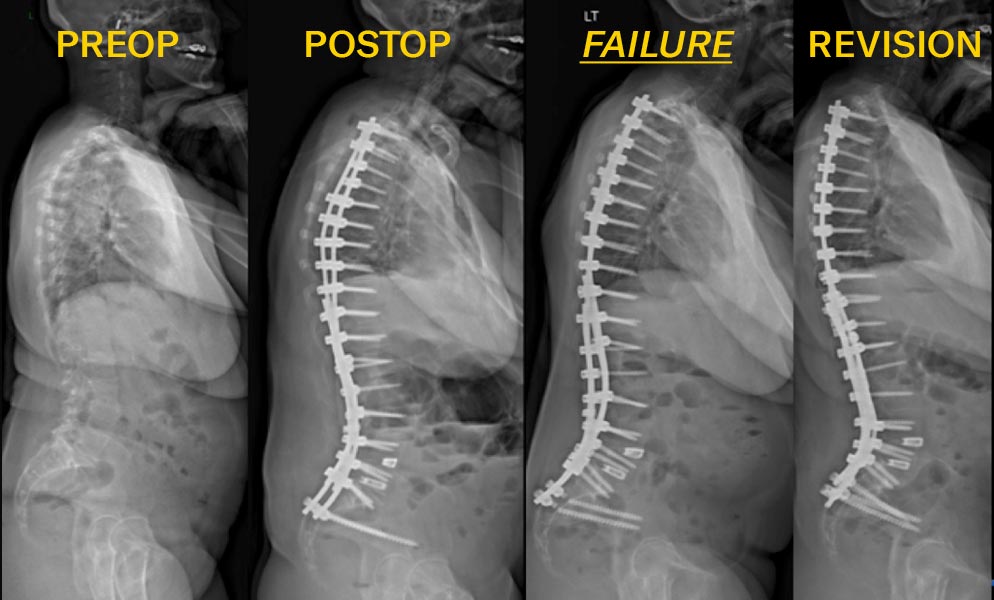

Radiology images of a female with adult idiopathic scoliosis who underwent posterior spinal instrumented fusion

A 57-year-old female with adult idiopathic scoliosis who underwent posterior spinal instrumented fusion from T2 to Pelvis with interbody fusions at L4-5 and L5-S1. Postoperatively, she had pseudarthrosis with bilateral iliac screw fractures. Revision surgery included re-instrumentation from T11 to the pelvis with 4 pelvic fixation points, 5 rods spanning the lumbo-pelvis with accessory rods anchored distal to S1.